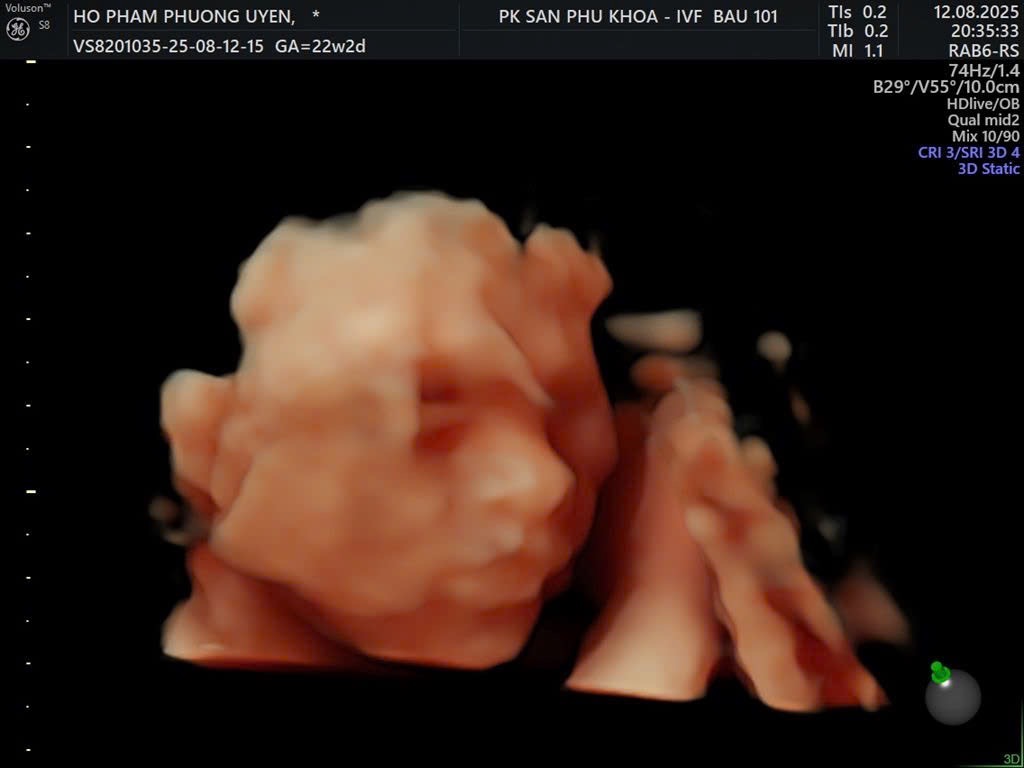

Hoàng Phạm Phương Uyên